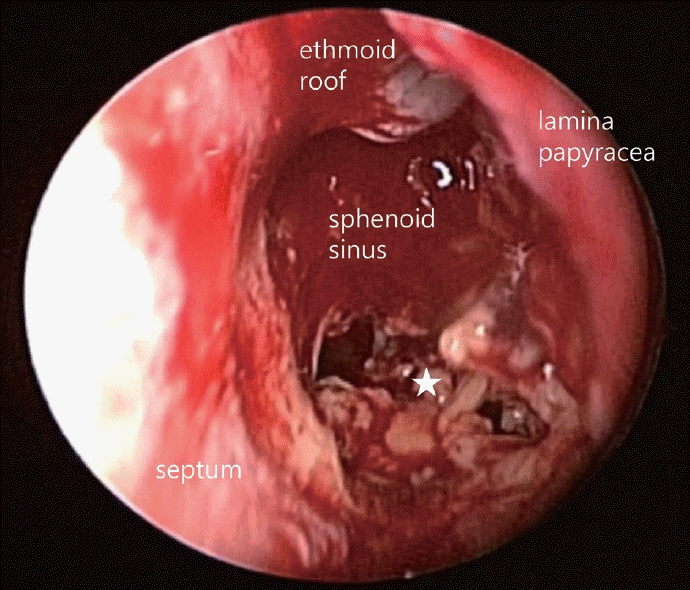

환자의 증상 및 영상소견을 종합하여 접형동을 침범한 악성종양을 의심하여 치료계획을 수립하기 위해 수술적 조직검사를 계획하였다. 영상학적 검사상 종괴가 시신경의 해부학적 주행과 인접하게 위치하여, 전신마취하에 수술을 시행하였으며, 부비동내시경 수술을 통해 좌측 후사골동 및 비강내 접형동 개방술을 시행하였다. 후사골동 및 접형동 내에는 점액농성의 분비물이 존재하였으며, 접형동 전외측 골결손 부위를 확인하였고 접형동 내벽에 존재하는 노란색과 회색을 띠는 부드러운 괴사성 조직을 확인하여 조직검사를 의뢰하였다(Fig. 2). 괴사성 조직은 대부분 제거하였으나 접형동 전외측 골결손 부위로 파급되어 있어 최종 조직병리검사 결과 확인 후 치료방침을 결정하기로 하였다. 수술 후 Merocel(Medtronic Inc., Minneapolis, MN, USA)을 이용하여 비강 패킹을 시행하였으며, 패킹은 수술 후 2일째에 제거하였고 환자는 수술 후 3일째에 특이 합병증 없이 퇴원하였다.

Intraoperative endoscopic findings. Intranasal sphenoidotomy and posterior ethmoidectomy were done, and sinuses were explored. Between yellow and gray-colored necrotic tissue (star) was exposed, and a biopsy was done.